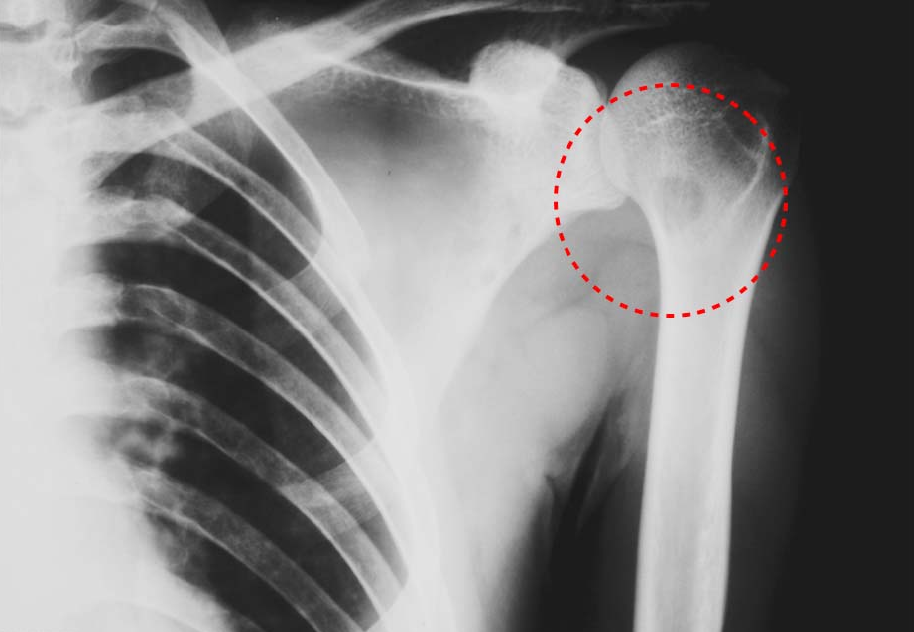

Figure3